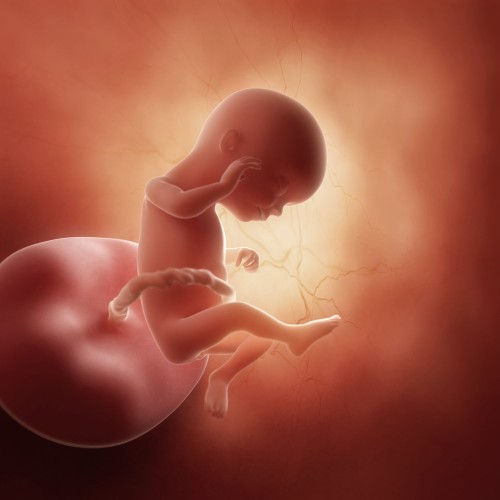

Ребенок на данный момент достигает роста около 109-117 мм и весит не менее 80 г. По своим размерам он напоминает авокадо и все еще свободно перемещается в материнской утробе. Объем околоплодных вод составляет примерно 250 мл.

У плода начинает формироваться тонкий слой мышечной ткани, что позволяет ему удерживать голову в вертикальном положении и поворачивать ее в разные стороны. Мышцы лица также становятся более развитыми, и малыш способен проявлять активные мимические реакции: хмуриться, открывать рот и даже подмигивать. У девочек на этом этапе яичники опускаются в малый таз, а влагалище, матка и фаллопиевы трубы уже развиты. У мальчиков формируются наружные половые органы, однако яички все еще находятся в брюшной полости.

Ребенок активно глотает околоплодную жидкость и может ощущать ее вкус. Почки и мочевой пузырь функционируют хорошо, поэтому плод мочится примерно раз в 45 минут. Околоплодные воды обновляются до 10 раз в сутки. Пуповина, соединяющая мать и плод и обеспечивающая его питательными веществами, на этом этапе располагается немного ниже, чем раньше.

На 16-й акушерской неделе беременности начинается формирование связочного голосового аппарата, однако малыш сможет издавать звуки только после рождения. В кожном покрове развиваются нервные окончания, что делает его очень чувствительным. При любом раздражении ребенок сжимает пальцы в кулачки и отодвигает руки и ноги при механическом воздействии на плодный пузырь.

Кровь плода уже сформирована, и на этом этапе можно определить ее группу и резус-фактор. Однако у ребенка все еще вырабатывается фетальный гемоглобин, который по своей структуре схож с кислородом. Обычно к концу первого года жизни он полностью заменяется на обычный гемоглобин.

Как выглядит плод на 16-й неделе беременности?

На 16-й неделе длина ребенка от копчика до темени составляет 108-116 мм, а вес около 80 гр. Чтобы легче представить размеры малыша, плод сравнивают со средним авокадо или с грушей. Лицо плода приобретает выраженные оформленные черты. Лоб выдвигается вперед, формируются носик и щечки.